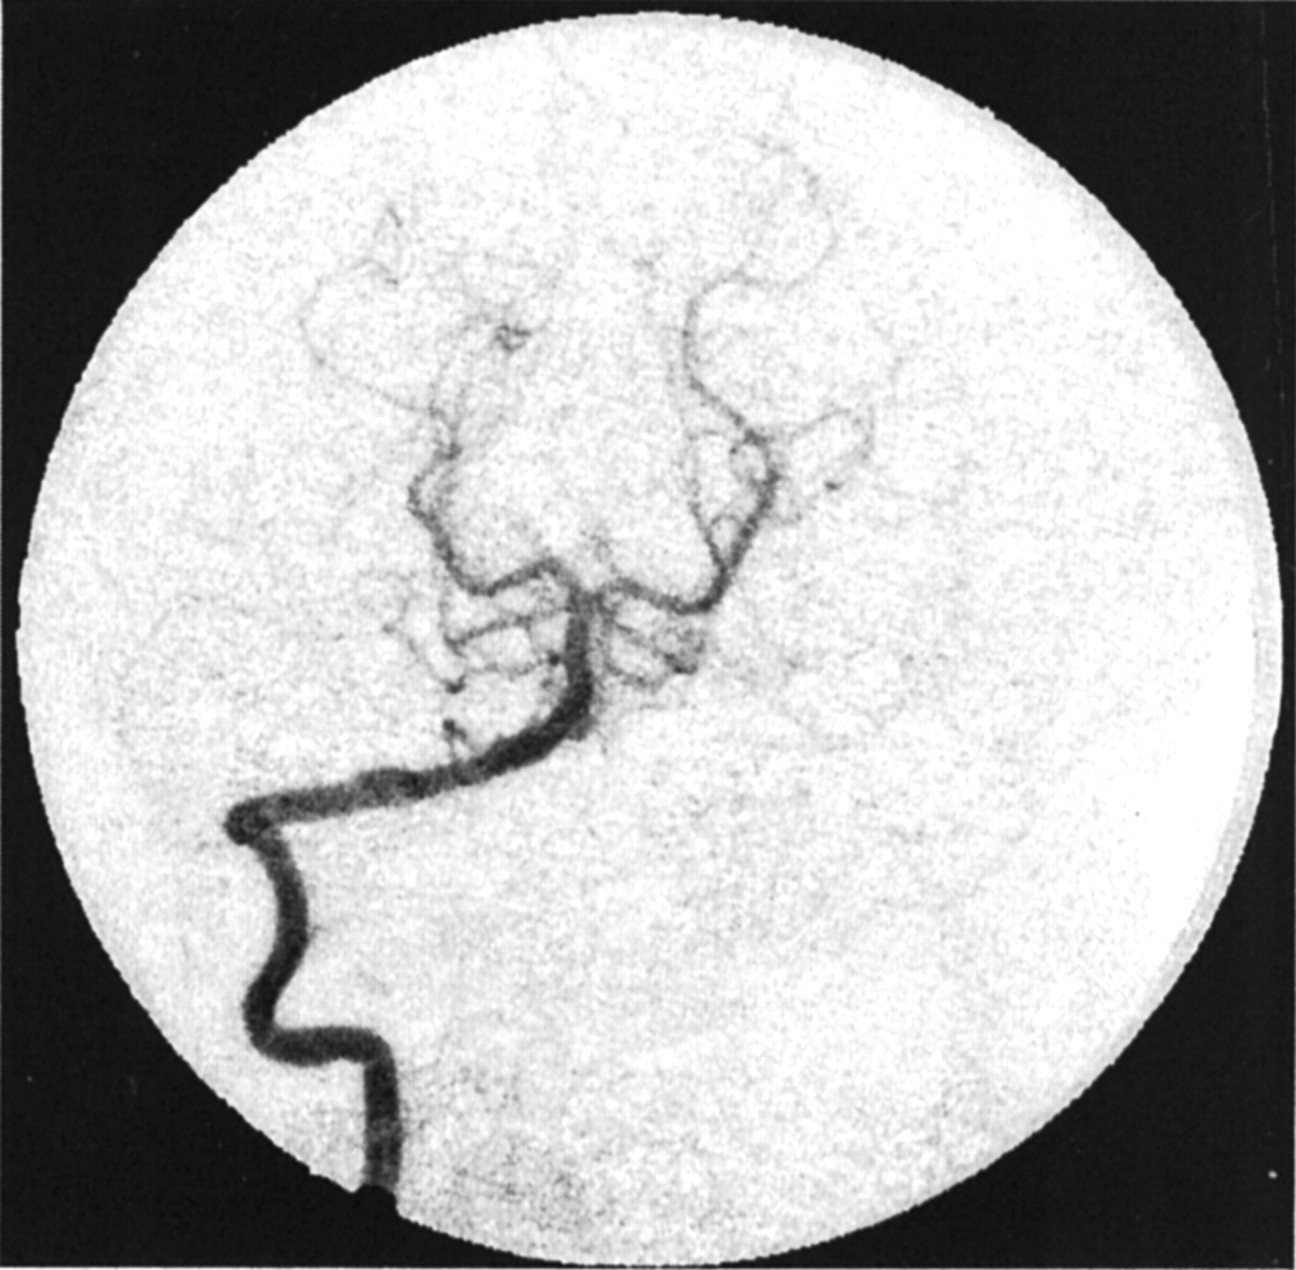

The frame in which the aneurysm was most clearly visualized was chosen in each angiographic run, and a polygonal region of interest (ROI) was manually traced around the aneurysm (Fig 3A). The ROI was traced by starting at the point where the aneurysmal projection in the frame deviated from the course of the normal artery. The tracing continued along the outer edge of the aneurysm and closed along the estimated edge of a normal artery at the aneurysmal neck. When arteries or draining veins are interposed with the aneurysmal mask, they erroneously contribute to the total gray-scale level when contrast material passes through them. In such cases, multiple ROIs that bypassed those arteries or veins were selected to generate the final mask (Fig 3B). That is, if any superimposing vasculature lay in the path of an ROI being traced, that ROI was closed by tracing back along the edge of the superfluous artery or vein. Another ROI was then started at the intersection of the path of the regular ROI trace and the other edge of the imposing vasculature. This mask was multiplied with the entire sequence of frames in a run that delineated the ROI in each frame. The average gray-scale intensity (total gray-scale value of pixels/total number of pixels) within the ROI was then calculated for each frame. Figure 4 shows the variations in average gray-scale intensity with time (raw concentration time curves), before and after stent insertion, from the in vitro experiment and from the anteroposterior (AP) projection data in patient 1.

Images in patient 1.

A, Angiogram illustrates the selection of an ROI.

B, Final mask.

Figures 8 and 9 show the model-fit curves before and after stent placement and the parameters obtained in clinical patient 1 (AP projection data), respectively. The magnitude of convection had been reduced by more more than half the value before stent insertion, whereas the diffusion magnitude and both time constants increased by more than twice their prior values. Therefore, the model could be used to predict increased flow stasis and increased likelihood of thrombosis of the aneurysm after stent placement. Figure 10 shows a follow-up angiogram obtained 3 months after stent implantation. The aneurysm, which was present at the vertebrobasilar junction (Fig 3A), had become completely thrombosed, and the angiogram showed normal vasculature.

Angiogram obtained at 3-month follow-up in patient 1 shows complete exclusion of the aneurysm from the circulation (AP projection).